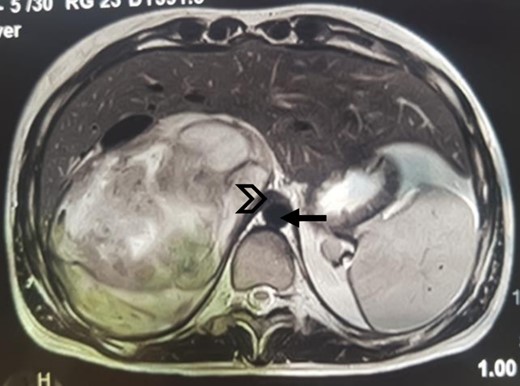

An MRI angiogram to assess the vascular relationships of the tumor revealed a 125 × 110 × 95 mm3 well-bounded, oval, slightly heterogeneous right adrenal mass with a mixed T2 signal and hypointense T1 signal. Angiographic sequences showed no portal venous thrombosis; the lesion was adherent to the right liver and the inferior vena cava (IVC), which was compressed but remained permeable, and came into contact with the superior mesenteric artery and the superior mesenteric vein, which were also permeable. The hepatic pedicle was also slightly pushed forward (Figs. 2 and 3).

MRI, well-limited oval right adrenal mass, slightly heterogeneous mixed T2 signal (arrow: aorta; arrowhead: compressed IVC).

MRI, voluminous lesion of the right adrenal medulla in hyposignal T1.